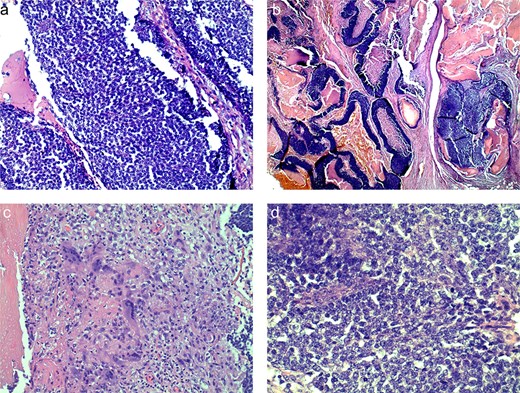

The preliminary pathology report revealed SLNs were negative for any evidence of granuloma or malignancy and showed sinus histiocytosis. The soft tissue mass reported size was 11.5 × 9.5 cm and resulted benign, as a PM. His case was submitted for second opinion consultation. The final pathology report showed an infiltrative and ulcerated tumor with matrical differentiation, high proportion of matrical/germinative cells with increased mitosis, and en masse necrosis (Fig. 4). This pathology was consistent with a PC. There were clear margins and no lymphovascular invasion.

Histologic slides demonstrating basaloid cells (a), nests of basaloid and shadow cells (b), cytoplasm of ghost cells (c), shadow cells with basophilic granules (d).